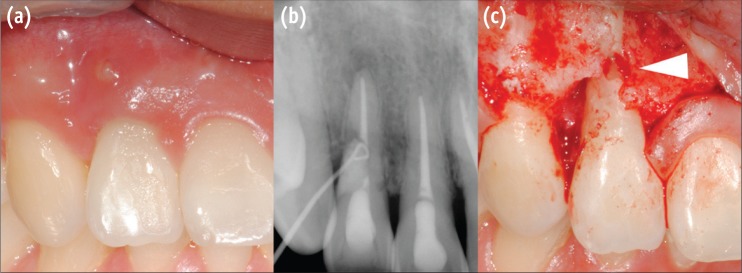

Thirty months after the trauma, the patient came to our department again for regular checkups. The patient was still free of symptoms, but there was a sinus tract formed on labial mucosa of right maxillary lateral incisor. Periapical radiograph was taken with gutta-percha tracing to confirm the origin. Surprisingly on the distal root surface of right lateral incisor, a noticeable cervical defect was revealed. The resorptive lesion was provisionally diagnosed as invasive cervical resorption and surgical repair was attempted (Figure 1).

One month recall showed satisfactory gingival healing and the patient was free of symptoms. However on the radiograph, suspicious radiolucent spot was observed under the glass ionomer filling, and after another month, sinus tract recurred. Periapical radiograph with gutta-percha tracing definitely shows apically advanced radiolucent lesion under the glass ionomer filling (Figure 3). Treatment options were discussed with the patient and decided to go on a re-surgery. Full-thickness periosteal flap was once more elevated. As predicted, the progressed resorption site was clearly seen under the buccal side of glass ionomer filling. After initial debridement, penetration points in the cavity were visible, again suggesting that there are tissues with active resorption potential left inside. Additional tooth preparation of the remaining resorptive tissue and glass-ionomer filling was done, but considering root stability and associated periradicular pathosis, we decided to extract the tooth (Figure 1).

Figure 3

(a) Recurred sinus tract 2 months after the surgery; (b) Periapical radiograph with gutta-percha tracing reveals the origin; (c) After opening the flap once more, advanced resorption below the glass ionomer filling was clearly seen (Arrowhead).